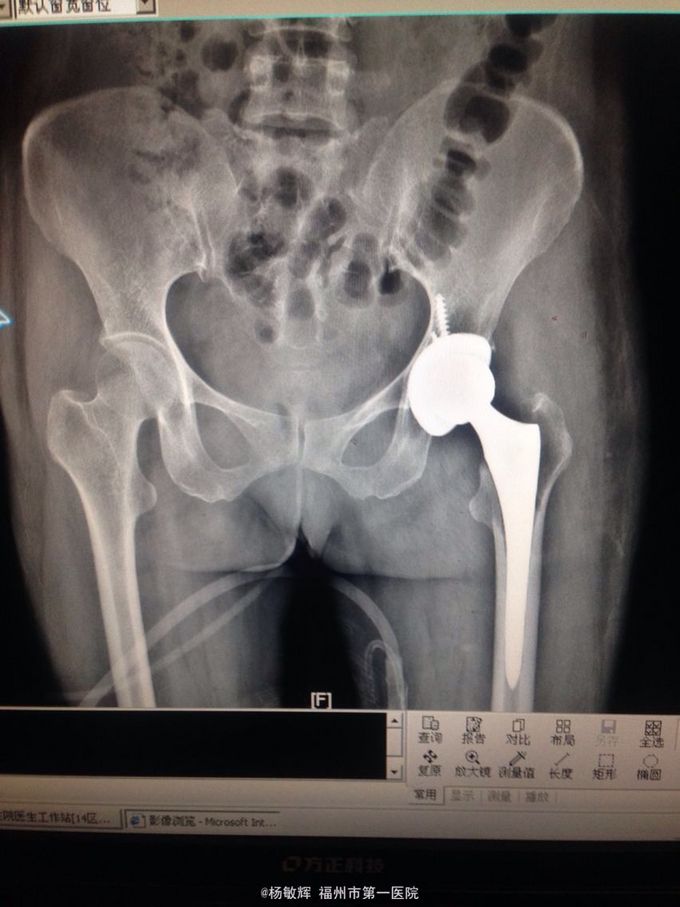

女性,48岁,以“左髋部疼痛伴活动受限2年”为主诉入院。缘于入院前2年无明显诱因出现左髋部疼痛不适,疼痛呈间歇刺痛,无向他处放射,伴左髋部活动受限,间歇性跛行,就诊当地医院查髋部X线提示:骨质破坏。MRI提示:左股骨头异常信号。当地医院诊断股骨头占位,未予以特殊处理,2周前疼痛加剧,就诊我院,查左髋部MRI提示:左髋部占位,骨巨细胞瘤可能性大。入院后于穿刺活检送病理,病理结果:左股骨头骨巨细胞瘤。拟:左股骨近段骨巨细胞瘤,收住院。

左股骨近段骨巨细胞瘤 入院后完善相关术前检查,未见明显手术禁忌症,行:左股骨近段占位切除+人工髋关节置换术